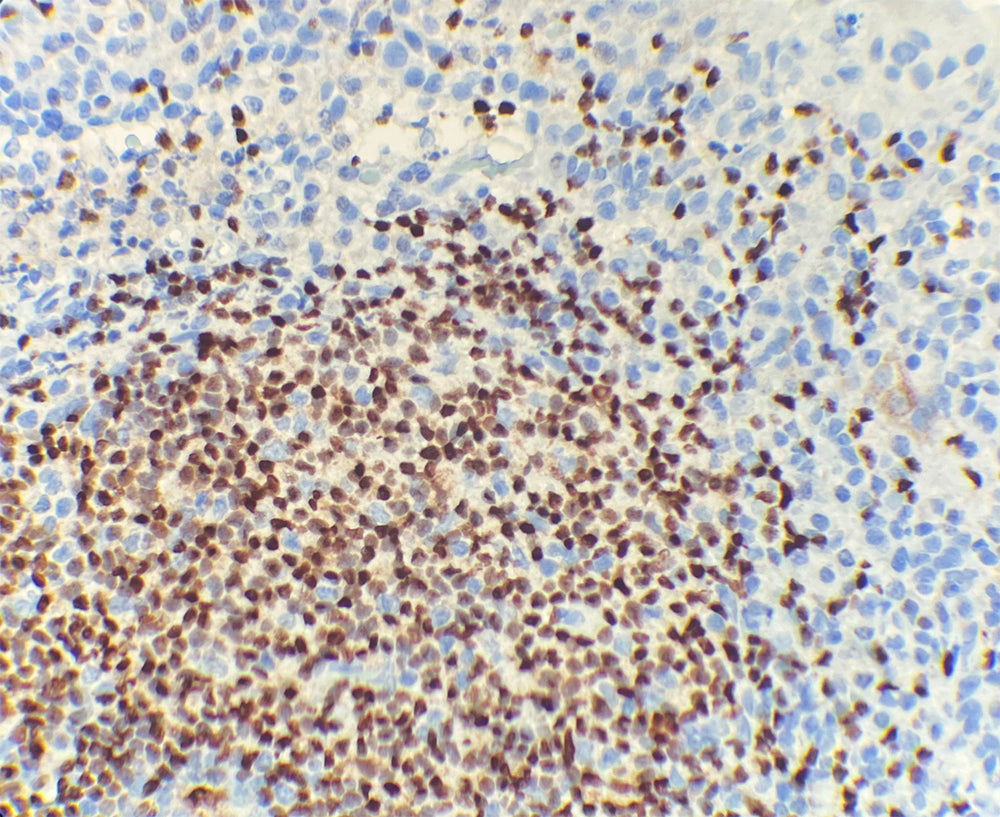

Contrôle positif : Tissu amygdalien